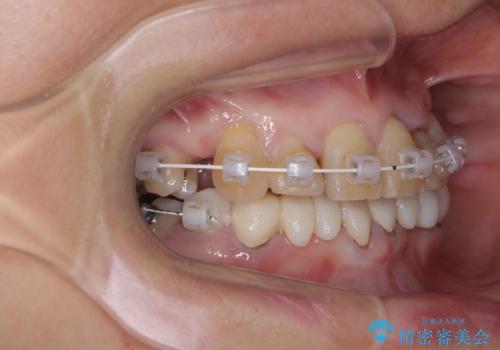

- 常に外れている下顎のブリッジと、前歯のデコボコと色を気にして来院された患者様です。

前歯のデコボコおよび奥歯の咬み合わせを改善するために、上顎左右の小臼歯を欠損スペースを利用して歯列を整え、矯正治療後に気になる上下前歯などをオールセラミッククラウンで美しく仕上げていくこととしました。